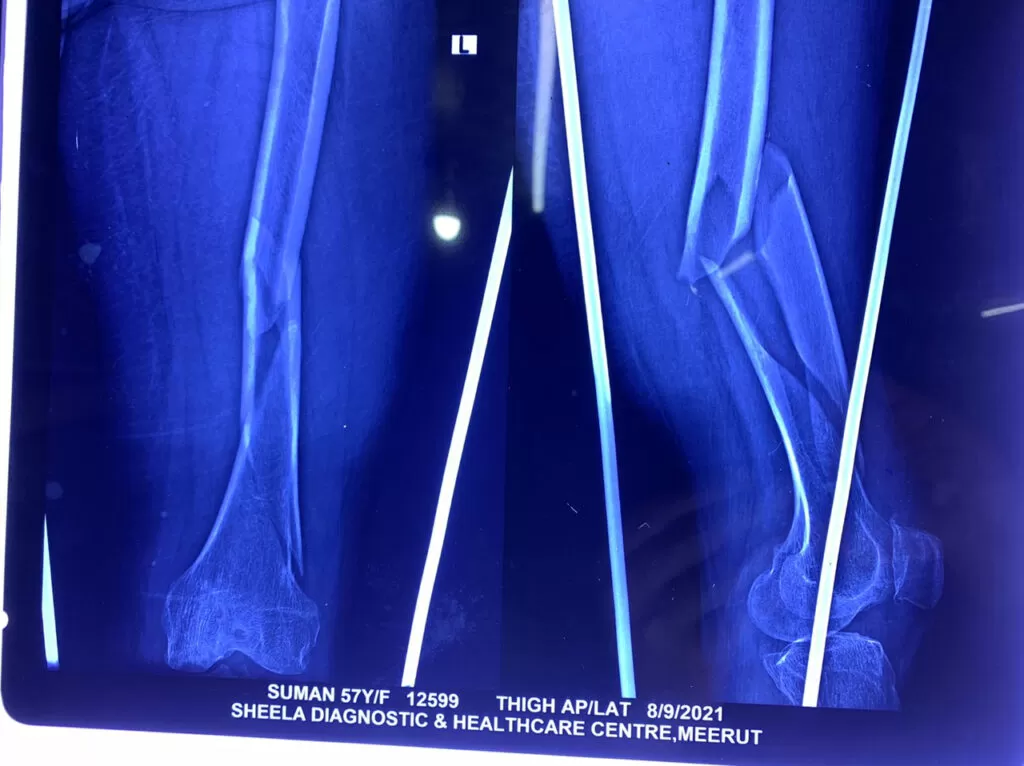

Mrs. Suman

Name: Mrs. Suman

Date of Operation: 8 Dec 2021

Age: 57 Years